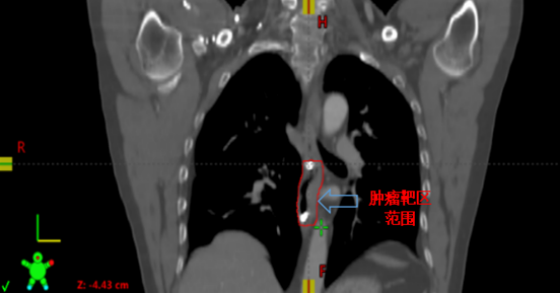

肿瘤靶区范围

接诊后,肿瘤科钟美佐主任同李军烽副主任医师结合患者既往病史和实际情况决定对病变部位实施放射治疗。考虑到患者食管病变较早,CT无法清晰显示病变部位及范围,患者曾经又接受过上段食管放射治疗,为进一步减少照射范围,准确定位肿瘤位置,肿瘤科联合消化内科,通过消化内镜在原位癌处附近植入金属钛夹标记物后再行增强CT,根据钛夹位置对病灶实施精准定位,尽可能的减少不必要的照射,降低患者放疗副作用的发生。目前高大哥已结束放射治疗,不适症状得到明显缓解。